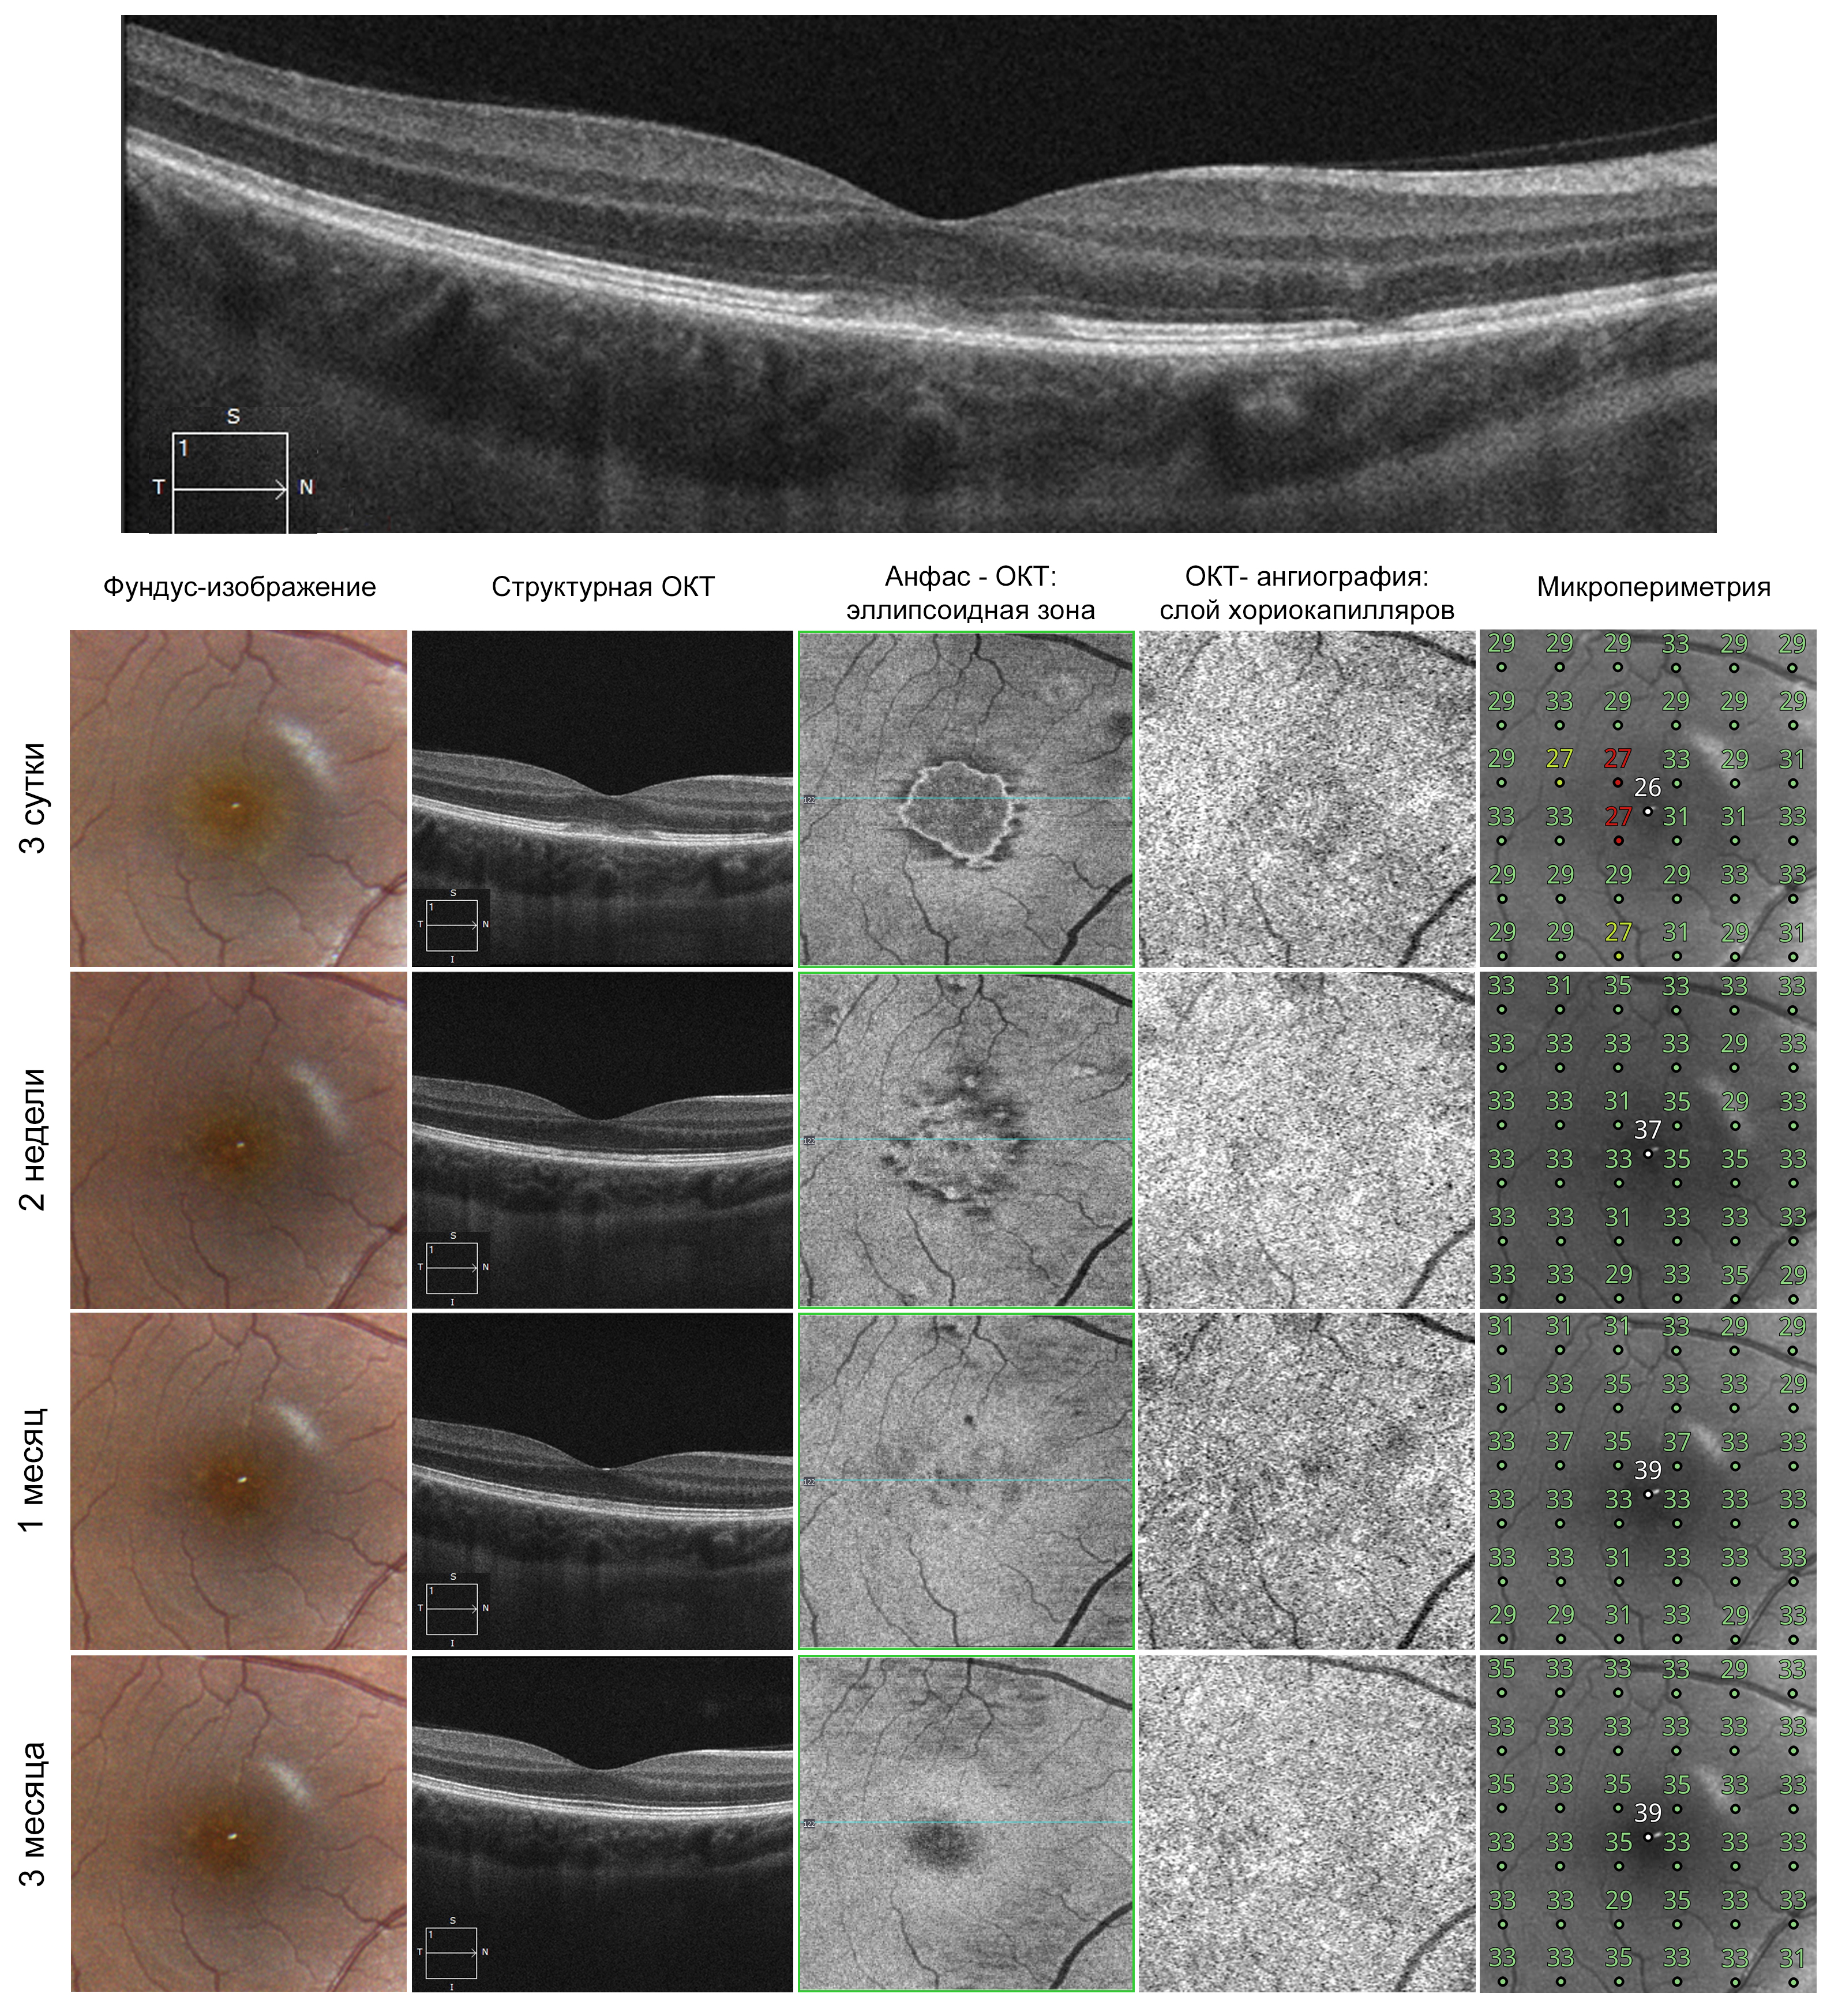

An OCT of the right eye showed a localized hyperreflective defect of the fovea at the level of the outer retina. This defect involved the myoid and ellipsoid zones of the photoreceptors, the outer segments of the photoreceptors, the interface of the photoreceptor segments with the retinal pigment epithelium (RPE) cells, and partially the outer limiting membrane (Fig. 1). Structural OCT sections nasal to the fovea showed another milder defect. According to full-field OCT data with segmentation at the level of the ellipsoid zone, the lesion area was up to 1 optic disc diameter. OCT-angiography showed a mild decrease in reflectivity at the level of the choriocapillaris in the projection of the lesion.

Microperimetry with the 10-2 grid (Compass, CenterVue) in the projection of the lesion at individual test points showed a decrease in light sensitivity, including the fixation point (Fig. 1).

Fig. 1. Results of multimodal diagnostic approach in patient A (explanations in the text)

A 2-week follow-up examination showed positive changes such as improvement of symptoms, a significant lesion reduction at the level of the ellipsoid zone on full-field OCT, and signs of restoration of the photoreceptor layer structure on structural sections (Fig. 1). In addition, structural OCT sections showed a decrease in the choroidal thickness in the projection of changes. Microperimetry showed increased retinal sensitivity to light in the lesion.

At the 1-month and 3-month follow-up visits, the patient had no complaints; OCT sections showed further complete restoration of the photoreceptor layer structure, and en face mode demonstrated resolution of the lesions at the level of the ellipsoid zone, while microperimetry revealed the increased retinal sensitivity to light at all tested points in the macula.

An OCT of the right eye showed a localized defect of the fovea at the level of the outer retina. This defect involved the myoid and ellipsoid zones of the photoreceptors, the outer segments of the photoreceptors, and the interface of the photoreceptor segments with the RPE (Fig. 2). However, hyperreflective material accumulated in the lesion at the RPE level, and the outer limiting membrane over the lesion was deformed, with its integrity preserved. En face OCT with segmentation at the level of the ellipsoid zone showed that the lesion involved the entire foveal region and the area of the lesion was 2/3 of the optic disc diameter. OCT-angiography showed a decrease in vascular signal at the level of the choriocapillaris in the projection of the lesion. However, accurate assessment of the choroidal thickness over time was complicated by signs of pachychoroid phenotype on structural OCT.

As in the first case, microperimetry with the 10-2 grid (Compass, CenterVue) in the projection of the lesion at individual test points showed a decrease in light sensitivity, including the fixation point (Fig. 2).

Fig. 2. Results of multimodal diagnostic approach in patient B (explanations in the text)

A 2-week follow-up examination showed no positive changes: complaints persisted; the full-field OCT area of the lesion did not change at the level of the ellipsoid zone, and focal changes remained on structural sections; hyperreflective material at the RPE level became more structured and compact, while there was no evidence of detachment or cystic changes in the neural retina (Fig. 2).

At 1-, 3-, and 6-months follow-up visits, the complaints remained the same, although the intensity of the spot in the visual field decreased; the best corrected visual acuity was restored to 1.0 at 1 month, and the structural OCT sections showed that the defect persisted, the ellipsoid zone remained partially damaged, and the en face area of its lesion was unchanged (Fig. 2).